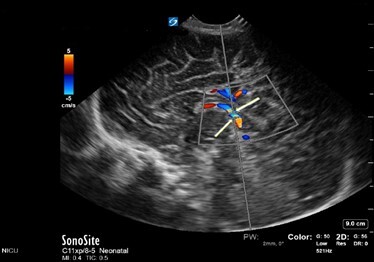

Neonatology Normal Anatomy Good Sample Gate Image